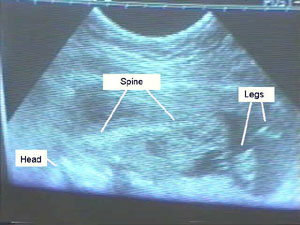

More From the Inside